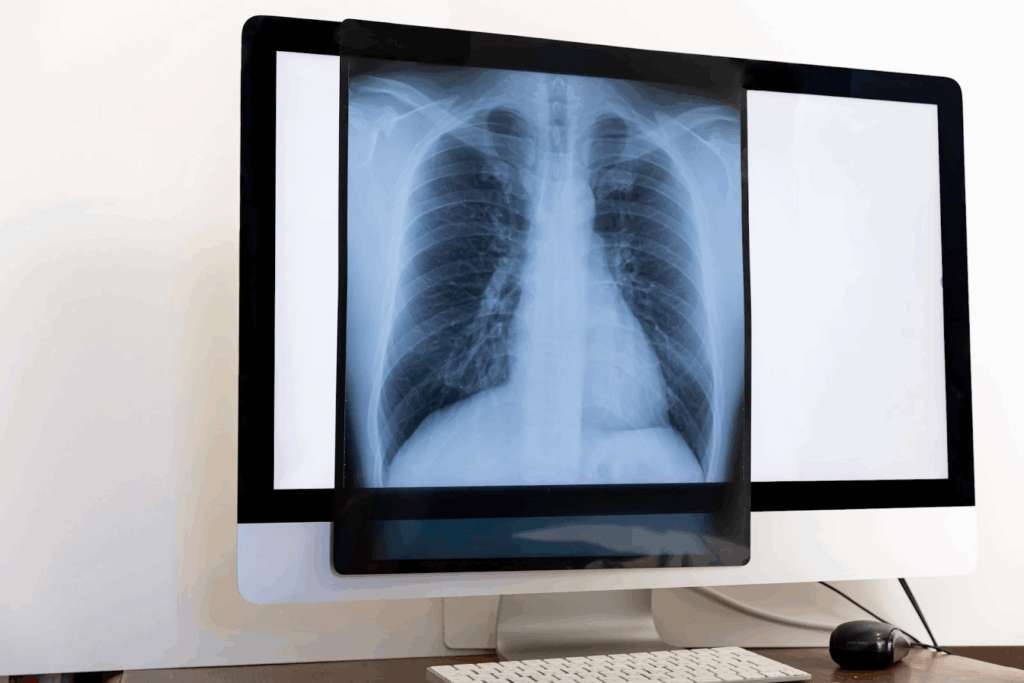

健康診断で「胸部レントゲンに異常があります」と告げられると、多くの人は不安を感じるでしょう。

すぐに重い病気を連想してしまいがちですが、実際には一時的な炎症の影や古い傷跡など、深刻ではないことも少なくありません。

それでも油断は禁物で、きちんと確認することで安心にもつながります。

胸部レントゲンは、健康診断でよく用いられる画像検査のひとつです。

受ける理由は、肺や心臓の病気を早めに見つけるため。

胸全体を一枚の写真に収めることで、大きな異常を拾いやすい仕組みになっています。

この検査で分かるのは、肺の中に「影」があるかどうか、心臓が通常より大きくなっていないか、肺炎や気胸(肺の空気が漏れる病気)といった病変の有無などです。

影の濃さや広がり方によって、炎症や腫瘤(しゅりゅう)の存在が疑われます。

胸部レントゲンは短時間で撮影でき、被ばく量も少なく安全性が高いのが特徴です。

ただし、CT検査に比べると詳細な情報は得られません。

小さな病変は写らないこともあるため、あくまで「ふるい分け」の検査と考えると安心です。